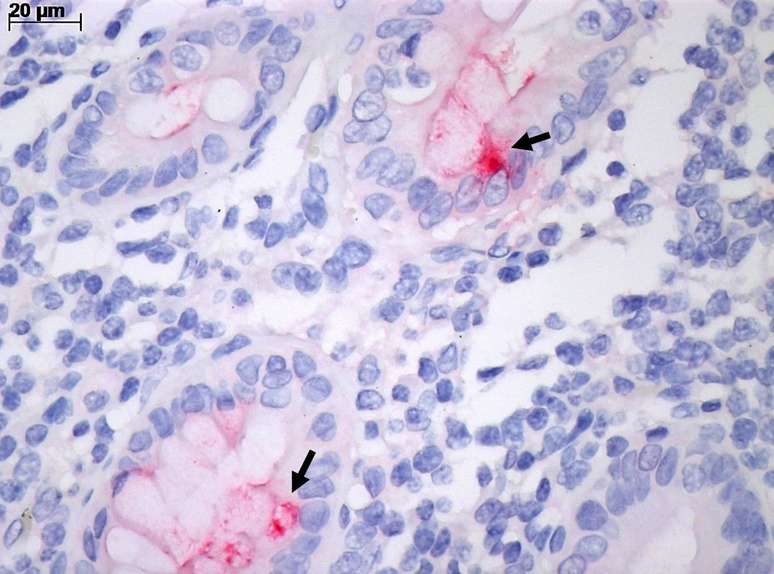

Intestino com inflamação pela covid-19, observado pelo microscópio comum. A coloração vermelha (seta) marca a infecção de célula intestinal pelo vírus SARS-CoV-2.

Foto: Cristina Kanamura / BBC News Brasil